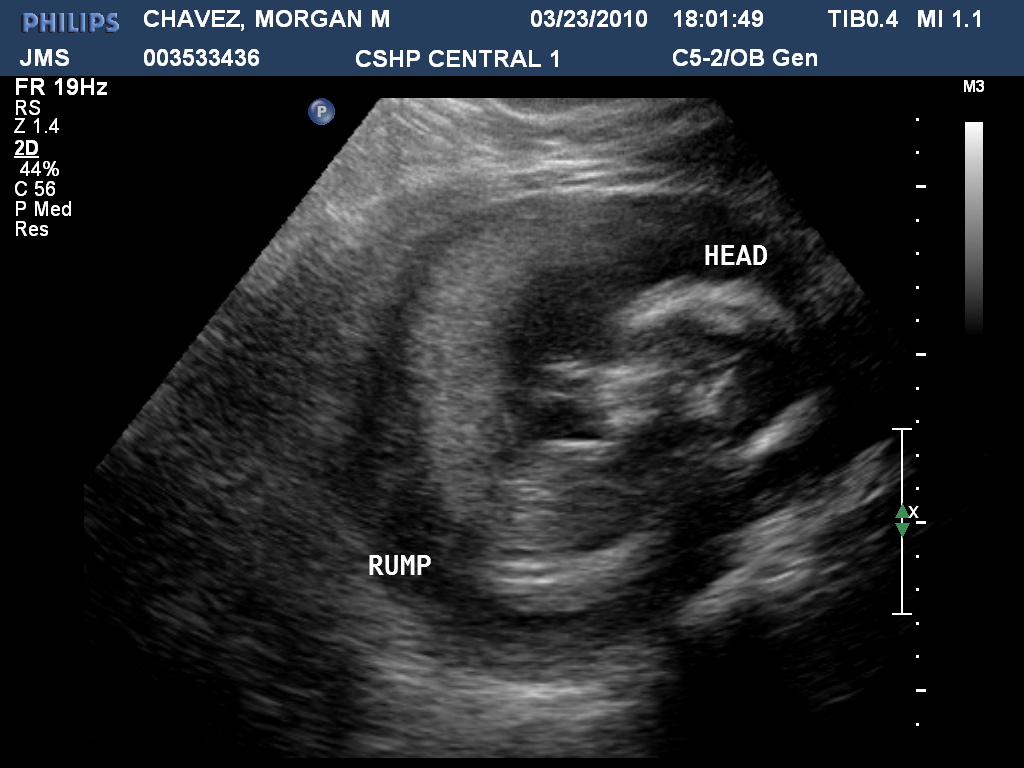

Yesterday was the ultrasound for the newest baby. We were hoping to find out if Amelia is going to have a baby brother or sister but such was not the case. I figured with all the ultrasounds we had with Amelia never showing us whether she was a boy or girls (27 total), that the odds would be with us to get a cooperative baby this time. We were able to see the heart, stomach, legs and feet really good but that is about it. The baby was moving so much we couldn't even get a good profile shot. The legs were tucks up so tight, not only were we not able to see the sex, the tech couldn't even see the kidneys or bladder or any other organs that they need to see. So I am hoping because of this they will order another ultrasound. If not I guess we will just have another surprise, which is fine too. As long as we get a healthy baby, that is all that matters. The really neat thing was they gave us all our pictures on a disc and even 2 videos. Here are the links for the videos, although they are harder to see because they are not labeled but it is neat to be able to see the baby move. http://www.youtube.com/watch?v=tS1TqBlsz_s http://www.youtube.com/watch?v=Mgogg2lUp74